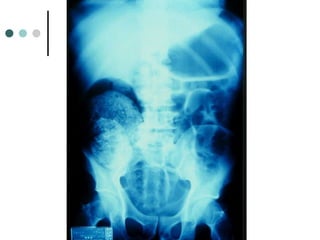

RADIOGRAFÍA SIMPLE DE ABDOMEN

Hemos de evaluar la presencia de diversas anormalidades:

Alteraciones del

Patrón aéreo

Masas

abdominales

Calcificaciones

Aire

intraluminal

extraluminal

• Íleo mecánico

• Íleo paralítico

• Abscesos

• Perforación de

víscera hueca

DE PIE

EN DECÚBITO

DORSAL

DECÚBITO PRONO

Niveles

hidroaéreos.

Niveles hidroaereos en ptes que no se

ponen de pie

El aire se desplaza hacia las

zonas laterales y a la ampolla

rectal.

Neumoperitoneo,

Neumo-patía

basal

Manifestación pulmonar

de patología

subdiafragmática.

Neumoperitoneo